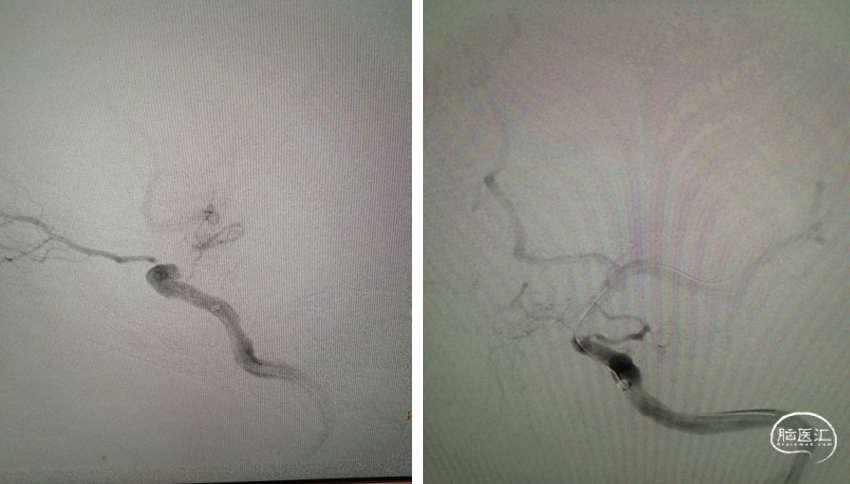

重要操作简述:中间支撑导管到位,并造影确认位于血管真腔内;注意穿支血管球扩前后变化。

导引导管到位,微导丝通过病变

球囊覆盖病变

重要操作简述:透视下缓慢球扩压力达到6ATM(并多个角度观察);病变段形态和有无造影剂外渗。

球囊扩张

扩张后造影